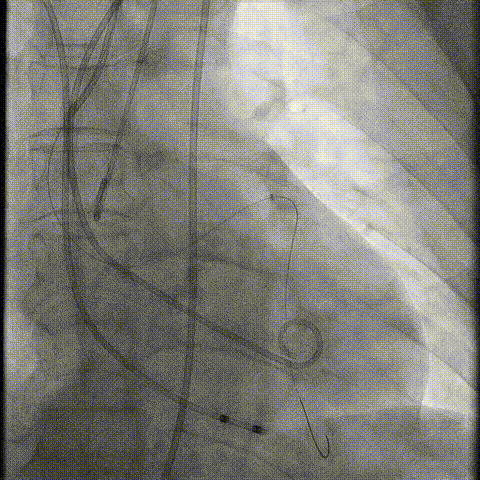

介入经过及结果

Telescope™+Runthrough

18mm*40mm 预扩张

预埋 Resolute Integrity 3.5*26mm

再次评估左冠开口

第一次释放

再次评估左冠开口,考虑调整瓣膜深度

回收后调整深度,再次释放

评估左冠开口

左冠开口切线位造影

决定左冠烟囱支架保护冠脉

调整支架位置

释放冠脉支架

释放瓣膜

造影评估

支架内后扩张

冠脉造影

根部造影

最终结果